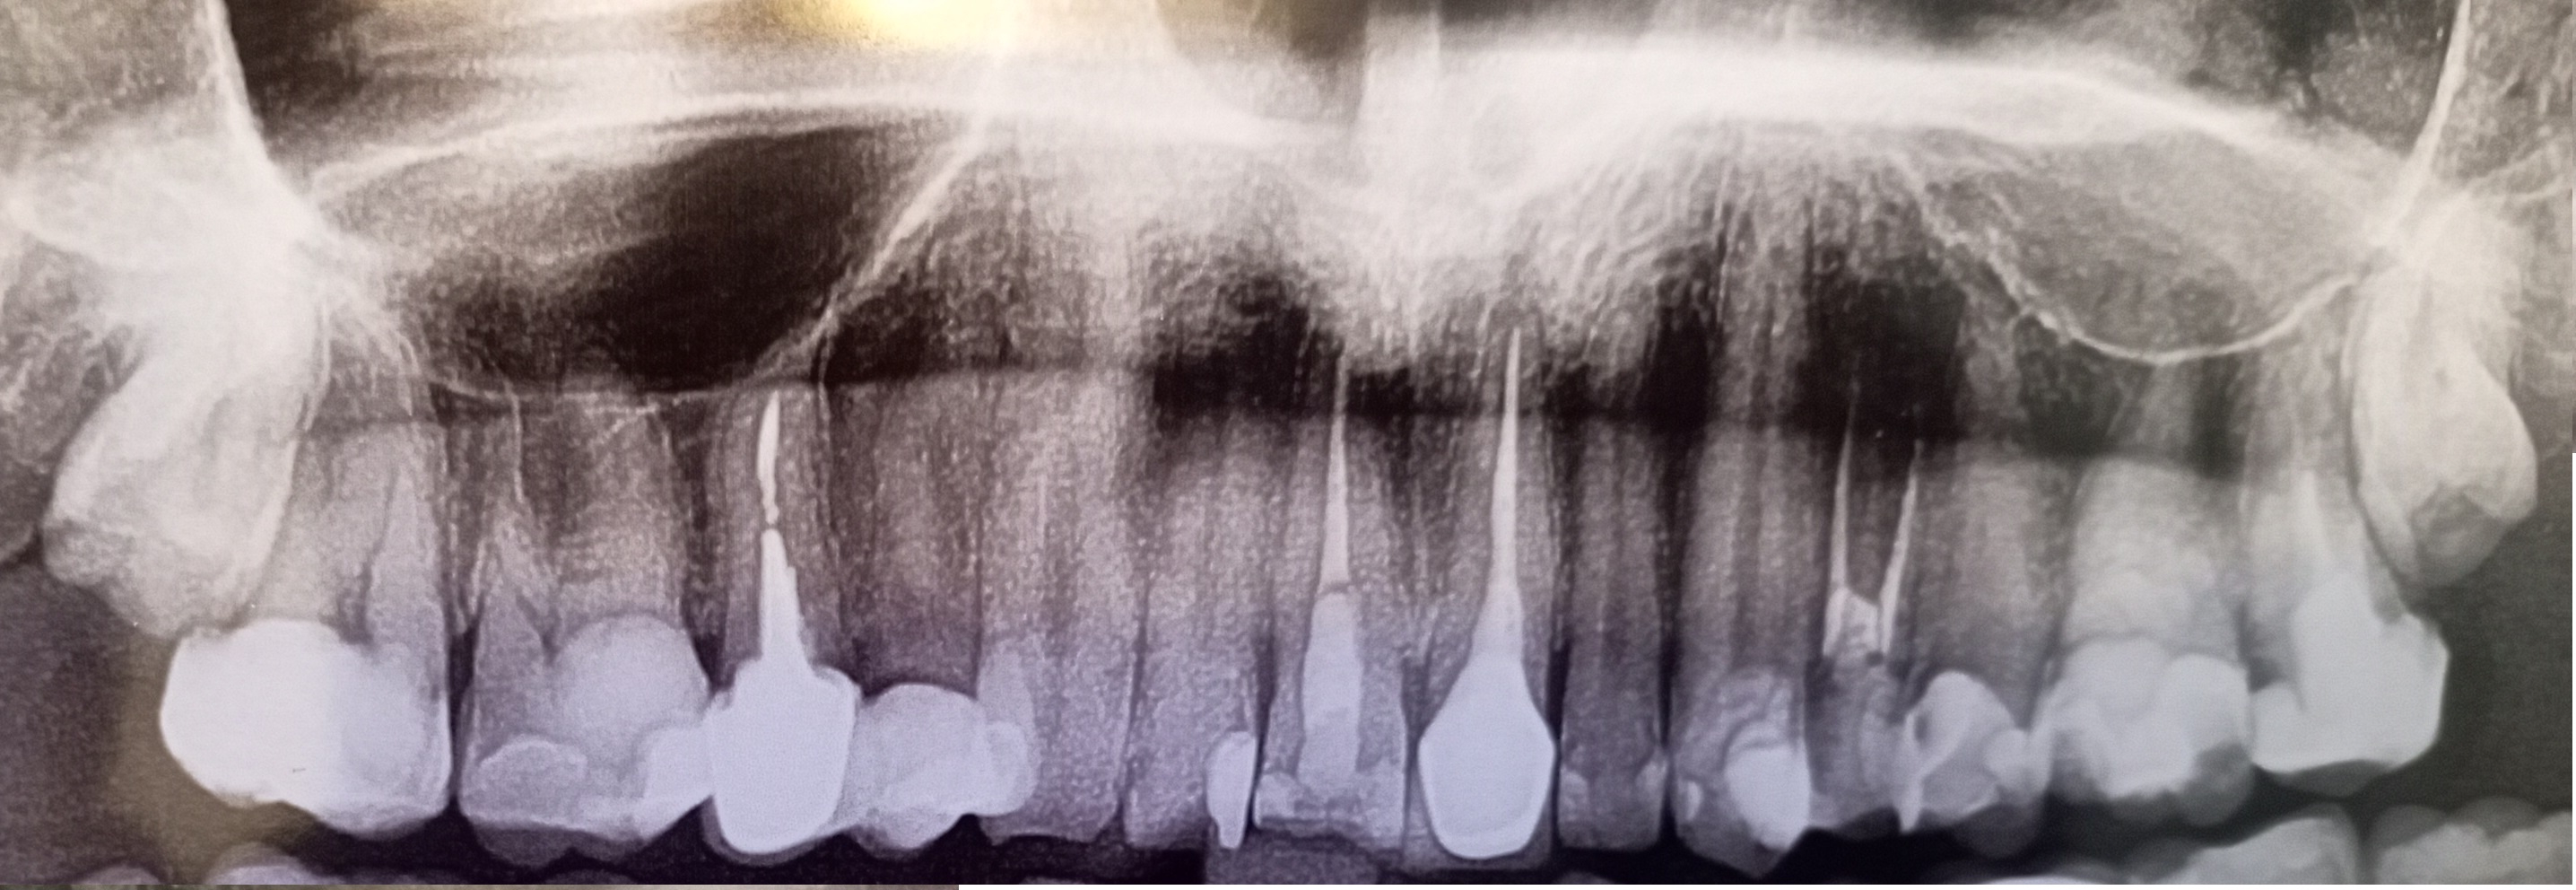

видел инфу, что стоит около 6 мес. после чистки и пломбы перед коронкой подождать, т.к. могут недолеченные каналы воспалиться или киста появиться и зуб с коронкой сразу на удаление.

Ходил 2 года по врачам, говорю зуб без нерва болит, в ответ - у тебя все збс, выдумываешь. Сходил в платку к студенту, он обнаружил огромную кариозную полость между зубами, зуб без нерва уже с кистой, а соседний полностью пульпитный.